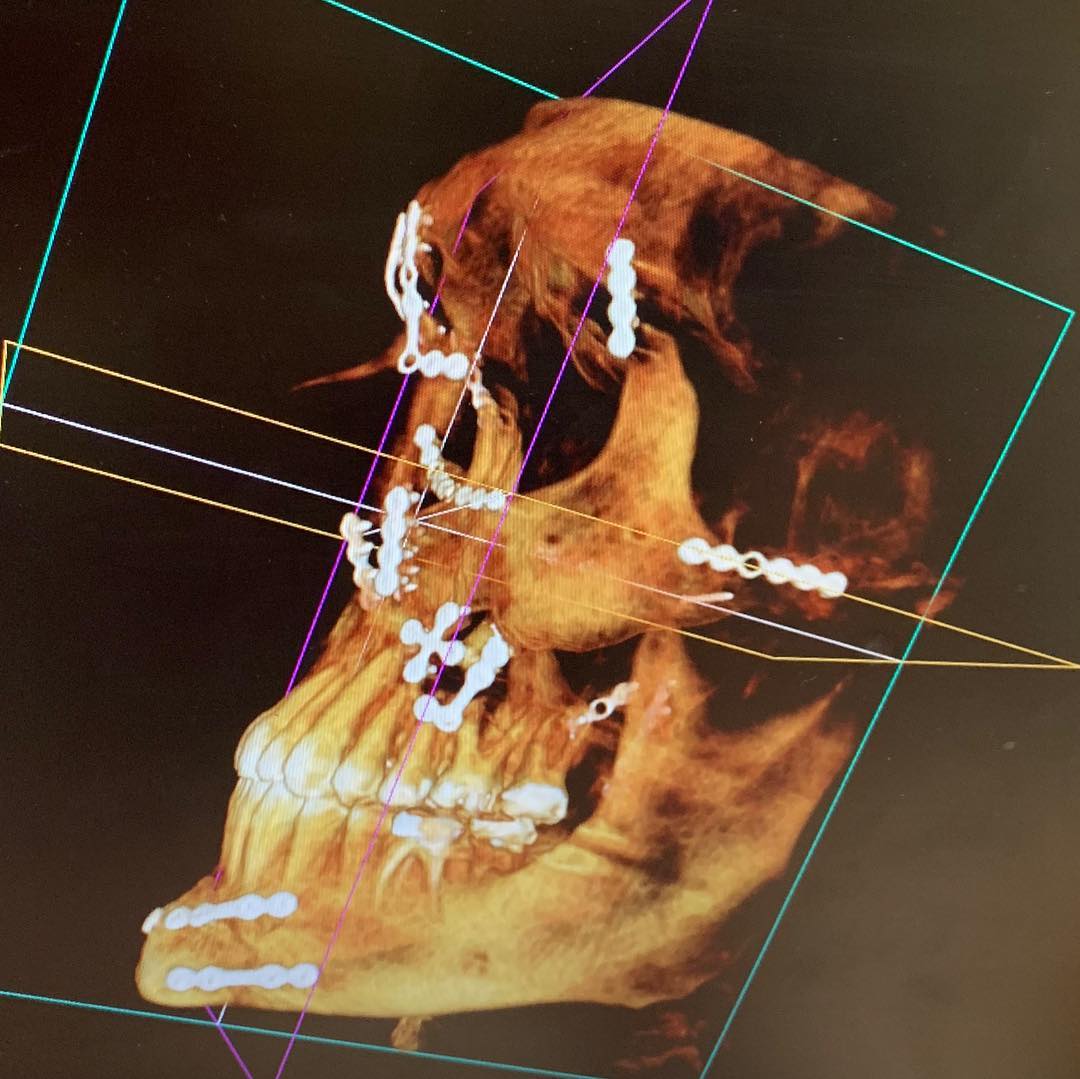

Weston Peick mostra a reconstrução do seu rosto

Weston Peick mostrou o quanto de trabalho foi necessário para reconstruir seu rosto após o acidente no Supercross de Paris, em novembro.

“21 placas quatro parafusos e um enxerto ósseo”, disse Peick sobre a cirurgia que ele teve que suportar após ser atropelado no primeiro main event da noite. Peick se recuperou bem, mas não foi divulgado se ele poderá voltar a competir.